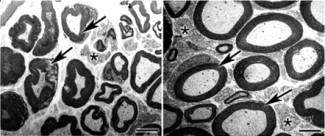

A medida que la diabetes fue avanzando se produjeron alteraciones en la estructura de la vaina de mielina que recubre el nervio ciático (izquierda). (Foto: DICYT)

Con la ayuda de un microscopio electrónico de transmisión, los científicos observaron que a medida que la diabetes fue avanzando se produjeron alteraciones en la estructura de la vaina de mielina que recubre el nervio ciático. Sin embargo, luego de las cuatro sesiones de fototerapia, la recuperación de la mielina fue prácticamente total.